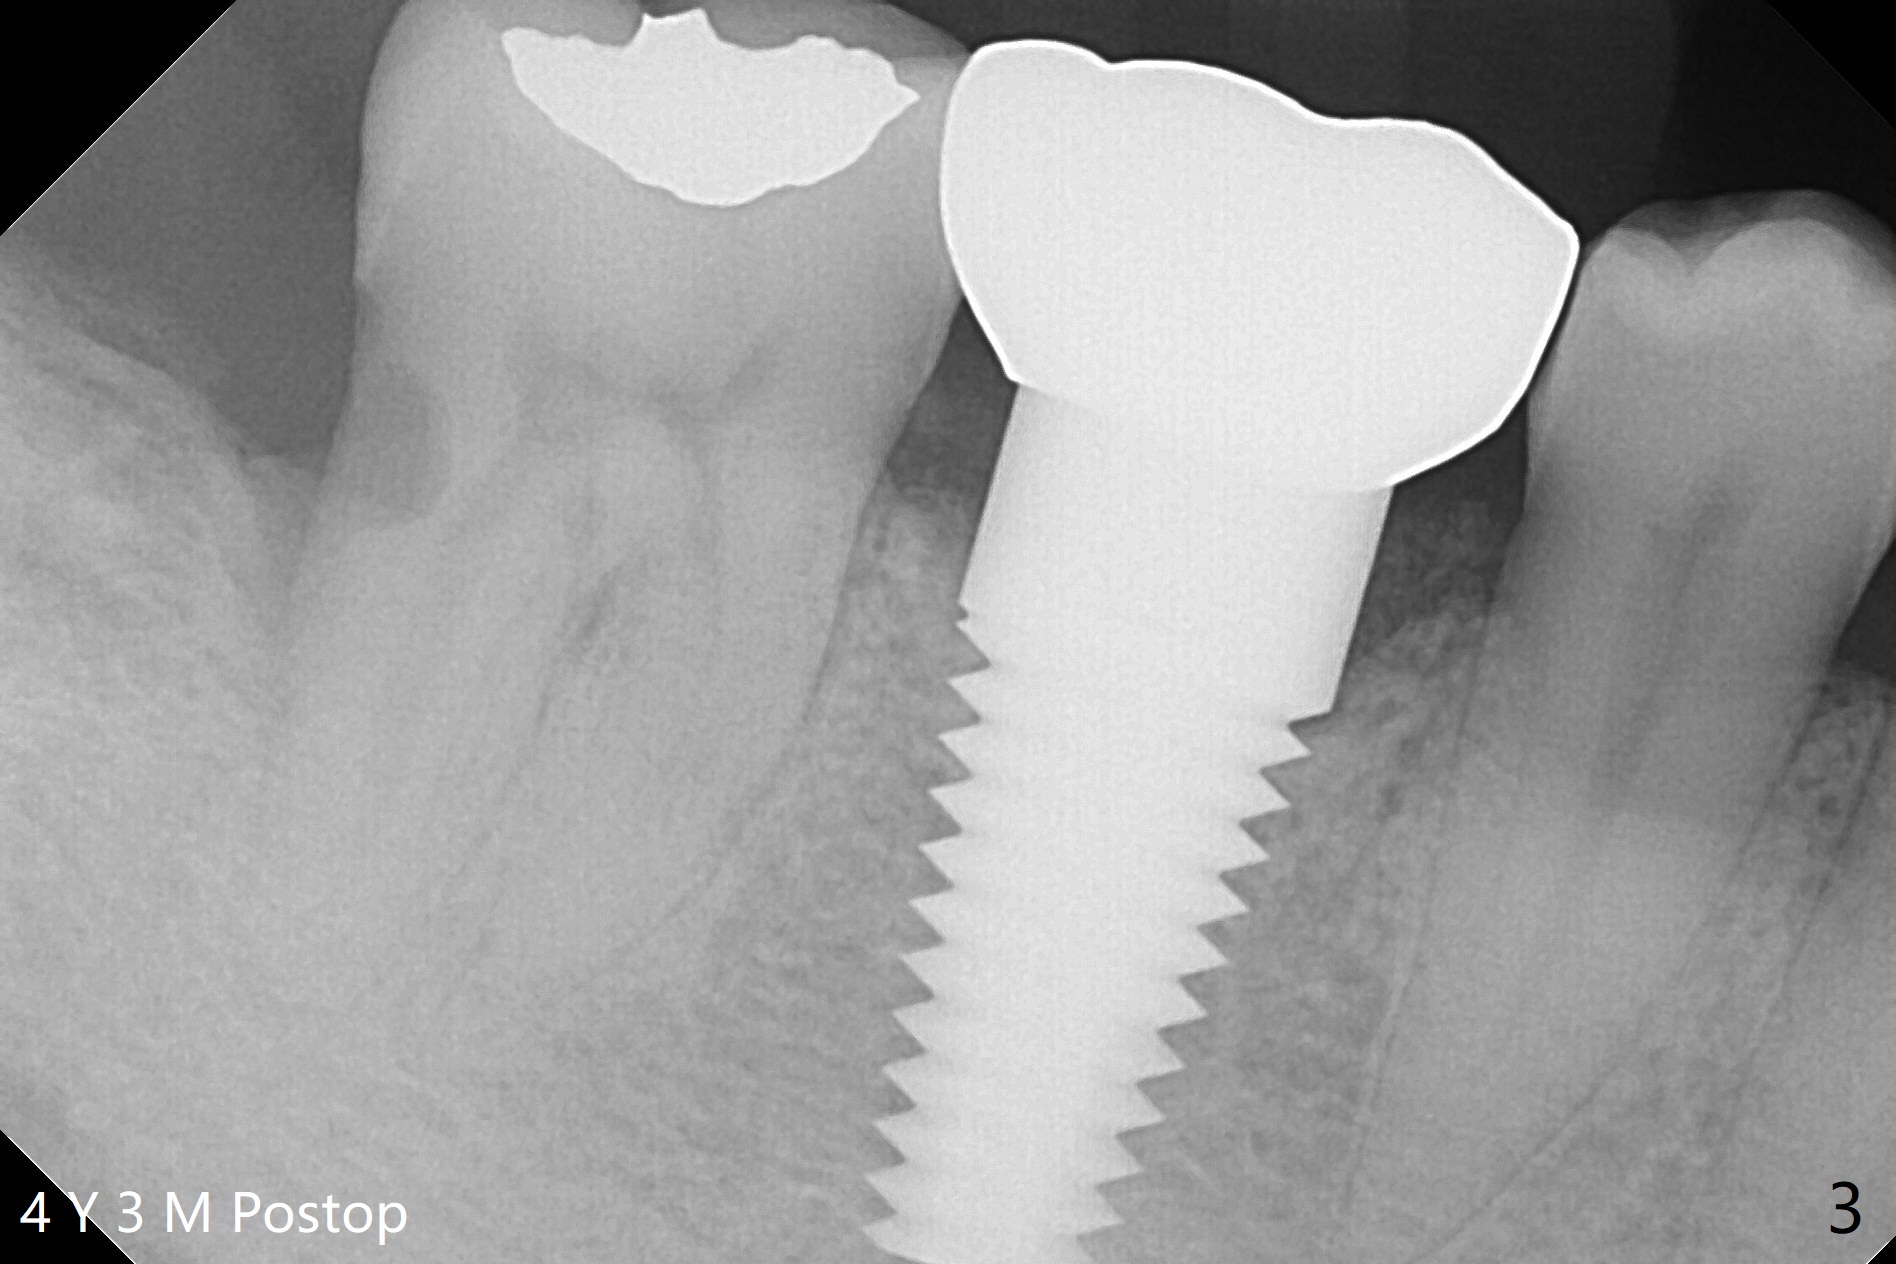

A 40-year-old man had the tooth #32 extracted without bone graft immediate post #30 implant placement (Fig.1,2). The distal bony defect of the tooth #31 appears to have been repaired 4 years postop (Fig.3,4).